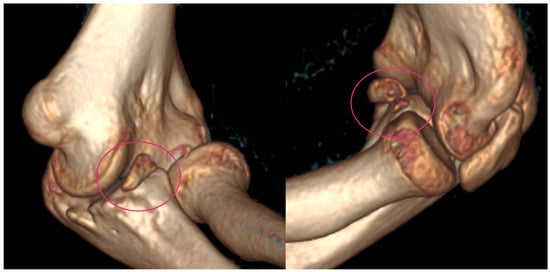

At the age of 13, another injury occurred, and the child complained of a sprain prior to the injury. X-ray imaging showed a posterior elbow dislocation without signs of a fracture (Figure 5). Under anesthesia, the luxation was repositioned. Following repositioning, an image review was performed, and no suspected fracture area was identified. A long upper limb cast was placed for two weeks.

Figure 5.

Imaging of the posterior dislocation at age 13, image (A) showing the luxation upon ebow extension and (B) from a lateral view in flexed position.

He suffered another elbow trauma due to a fall at the age of 14, resulting in pain and dislocation. X-rays showed no recent fracture, but a 5 mm rounded bone fragment was visible. MRI was requested for diagnostic purposes and further exploration (Figure 6). The results indicated that the fragment originated from the coronoid process and that the elbow was in a dorsally subluxated position. With regard to the instability, the exploration of the joint with debridement and reconstruction was proposed. A CT scan was performed for surgical planning, which yielded equivalent results to the MRI. A summary of events can be seen in Table 2.

Figure 6.

X-rays showing fragmentation, highlighted by the pink circle (A,B). Subluxation is visible on the MRI pointed at with pink arrows (C).